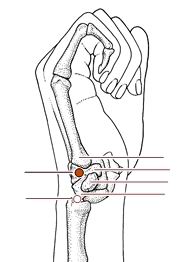

神门穴

经穴名。出《针灸甲乙经》。《难经·六十六难》名兑骨。别名兑中、中都、锐中。属手少阴心经。输(土)、原穴。在腕部,腕掌侧横纹尺侧端,尺侧腕屈肌腱的桡侧凹陷处。布有前臂内侧皮神经,尺神经及尺动脉。主治心痛心烦,惊悸怔忡,健忘失眠,癫狂,痫症,目黄,失音,喉痹,胁痛,腕关节痛等。直刺0.3-0.5寸。艾条灸5-10分钟。

阳溪

经穴名。出《灵枢•本输》。别名中魁。属手阳明大肠经。经(火)穴。在腕背横纹桡侧,手拇指向上翘起时,当拇短伸肌腱与拇长伸肌腱之间的凹陷中。布有桡神经浅支,头静脉、桡动脉本干及其腕背支。主治头痛,目赤肿痛,齿痛,咽喉肿痛,耳聋,手腕痛等。

腕骨穴

腕骨穴是手太阳小肠经上的腧穴之一,在手掌尺侧,当第5掌骨基底与钩骨之间,赤白肉际凹陷处,在手背尺侧,小指展肌起点外缘;有腕背侧动脉,手背静脉网;布有尺神经手背支。主治指挛腕痛、头项强痛;目翳;黄疸;热病、疟疾。操作方法为直刺0.3-0.5寸。